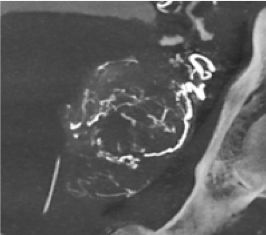

Vessel ASSIST für periphere Verfahren

Bei peripheren, chronischen Komplettverschlüssen (CTO) bietet die Vessel ASSIST-Lösung eine intuitive und genaue Lösung, die Sie bei der Planung und Führung komplexer endovaskulärer CTO-Eingriffe unterstützt. 1

Die automatische Segmentierung von Knochen und Gefäßen und die Mittellinienverfolgung durch den Gefäßverschluss ermöglichen eine schnelle Planung anhand von präoperativen CT- oder MR-Bildern. Durch diese Kombination präoperativer CT- oder MR-Bilder mit Mittellinienverfolgung und Durchleuchtung in Echtzeit können Spezialisten außerordentlich gut sehen, wo die Rekanalisation vorgenommen werden muss und wo sich die Einstichstelle befindet, ohne die Kontrastmittelmenge erhöhen zu müssen.

Vessel ASSIST bietet eine präzise und einfache anatomische Segmentierung und genaue Gefäßquantifizierung anhand von 3D-Volumen. Zudem ermöglichen die erweiterte 3D-Roadmap und erweiterte Bildführungsfunktionen für die frontale und laterale Ebene das sichere Führen von Kathetern.